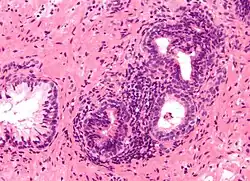

| Micrograph showing an inflamed prostate gland, the histologic correlate of prostatitis. A normal non-inflamed prostatic gland is seen on the left of the image. H&E stain. | |